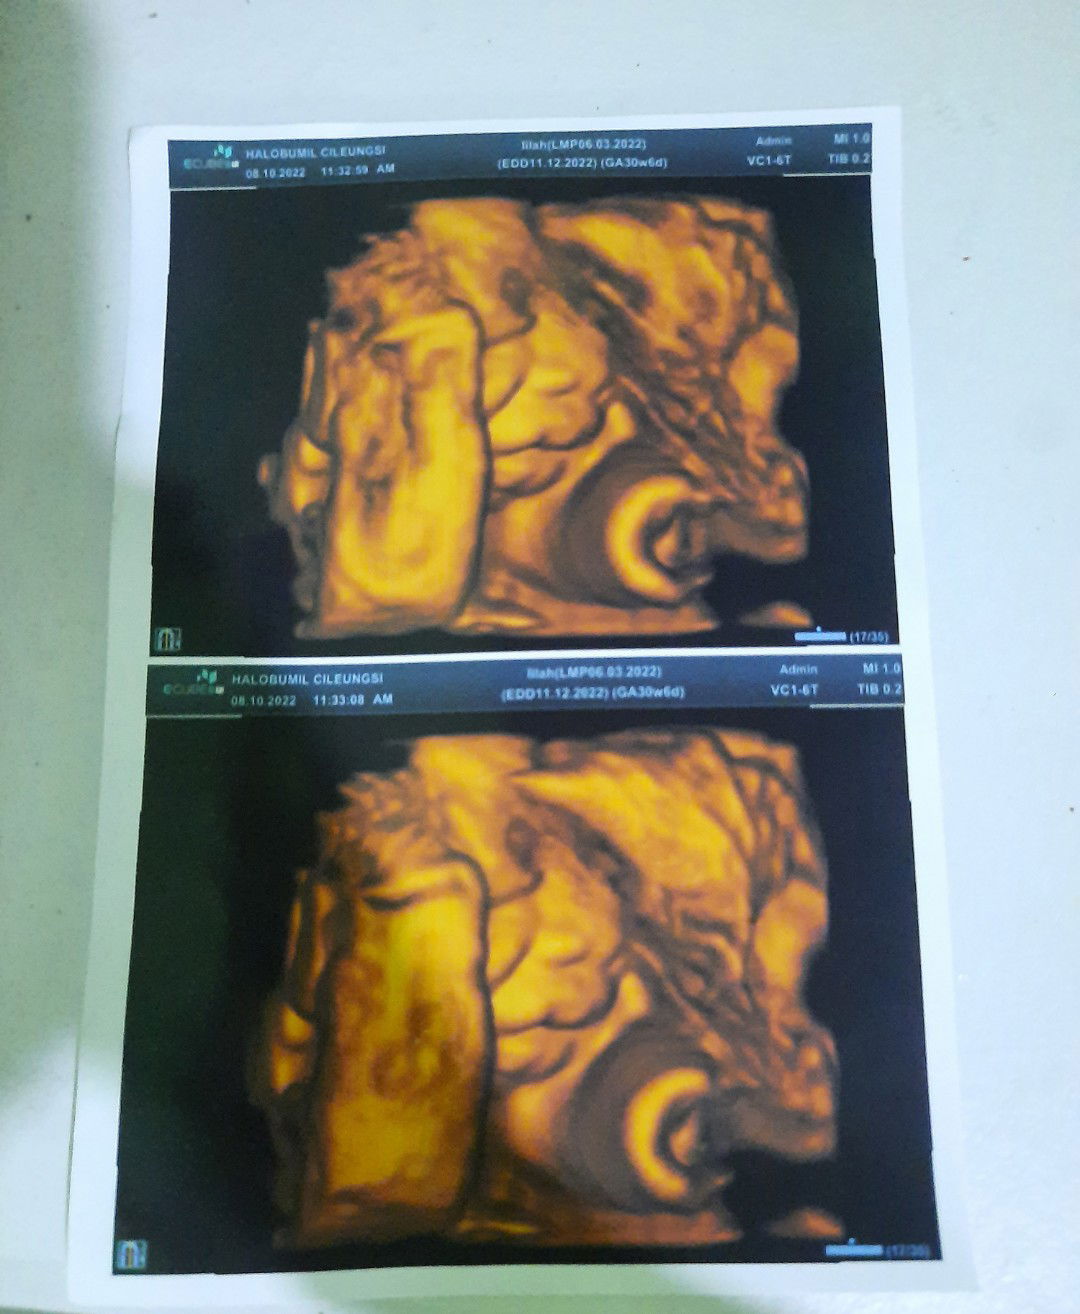

Bunda² yg hplnya Desember , Dd bayinya ada yg belum msk panggul blm? Aku blm msk hpl tgl 12

Hpl Desember